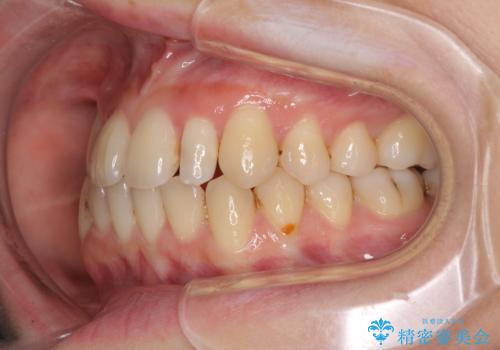

八重歯の抜歯矯正 補助装置を用いたインビザライン矯正

- 上顎の重なっている前歯を気にして来院された患者様です。

重なっている部分は抜歯が必要で、歯の移動量が多く、更には右側にずれている正中を改善する必要がありました。

インビザライン単体での治療は困難と判断し、補助装置により八重歯移動後にインビザラインを用いることとしました。

非常にしっかりとマウスピースを装着してくださいましたが、前歯の排列がなかなか仕上がらずに期間がかかってしまいました。